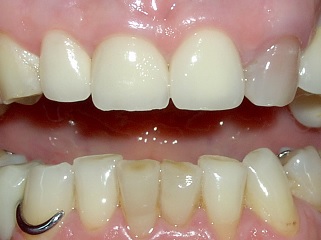

Gli elementi più frequentemente interessati sono gli incisivi superiori, in particolar modo gli incisivi centrali.

Dopo un trauma che porta alla frattura di un elemento dentale occorre:

L'odontoiatra, dopo aver valutato il danno, escluso eventuali fratture, controllato la mobilità e la vitalità degli elementi interessati, provvederà alla pianificazione degli interventi necessari.

Se ci si trova in presenza di esposizione della polpa, come si può vedere nella foto a lato, quest'ultima potrebbe aver subito un danno e potrebbe rendersi necessaria la sua rimozione; se gli elementi traumatizzati presentano mobilità in seguito a microfratture della corticale ossea in cui sono inseriti può rendersi necessario immobilizzarli per un periodo legandoli agli elementi adiacenti.

Frequentemente possono essere presenti concomitanti lesioni lacerocontuse al labbro, in tal caso l'odontoiatra valuterà l'eventualità di posizionare qualche punto di sutura.

Se non è stato possibile rinvenire i frammenti fratturati, la ricostruzione può avvenire in due modi, direttamente in bocca al paziente oppure rilevando un'impronta, facendo eseguire la ricostruzione delle parti mancanti ad un bravo odontotecnico e provvedendo successivamente alla loro cementazione.

Senza dubbio la situazione più favorevole è quella in cui si hanno a disposizione i frammenti originali, in tal caso è possibile, con buona padronanza della tecnica, reincollarli, limitando al massimo le discrepanze di forma e colore, con un risultato molto stabile nel tempo.

Qualora ciò fosse possibile, è sempre di primaria importanza intervenire tempestivamente per risolvere quanto prima il trauma psicologico della perdita dell'integrità dell'immagine di sè. Il piccolo paziente arriva in studio sempre molto preoccupato per il danno permanente che si è creato e riuscire a "cancellarlo" rapidamente, e in modo valido dal punto di vista estetico, crea un immediato giovamento che si riflette positivamente sulla sua salute psicologica e di tutto il nucleo familiare.